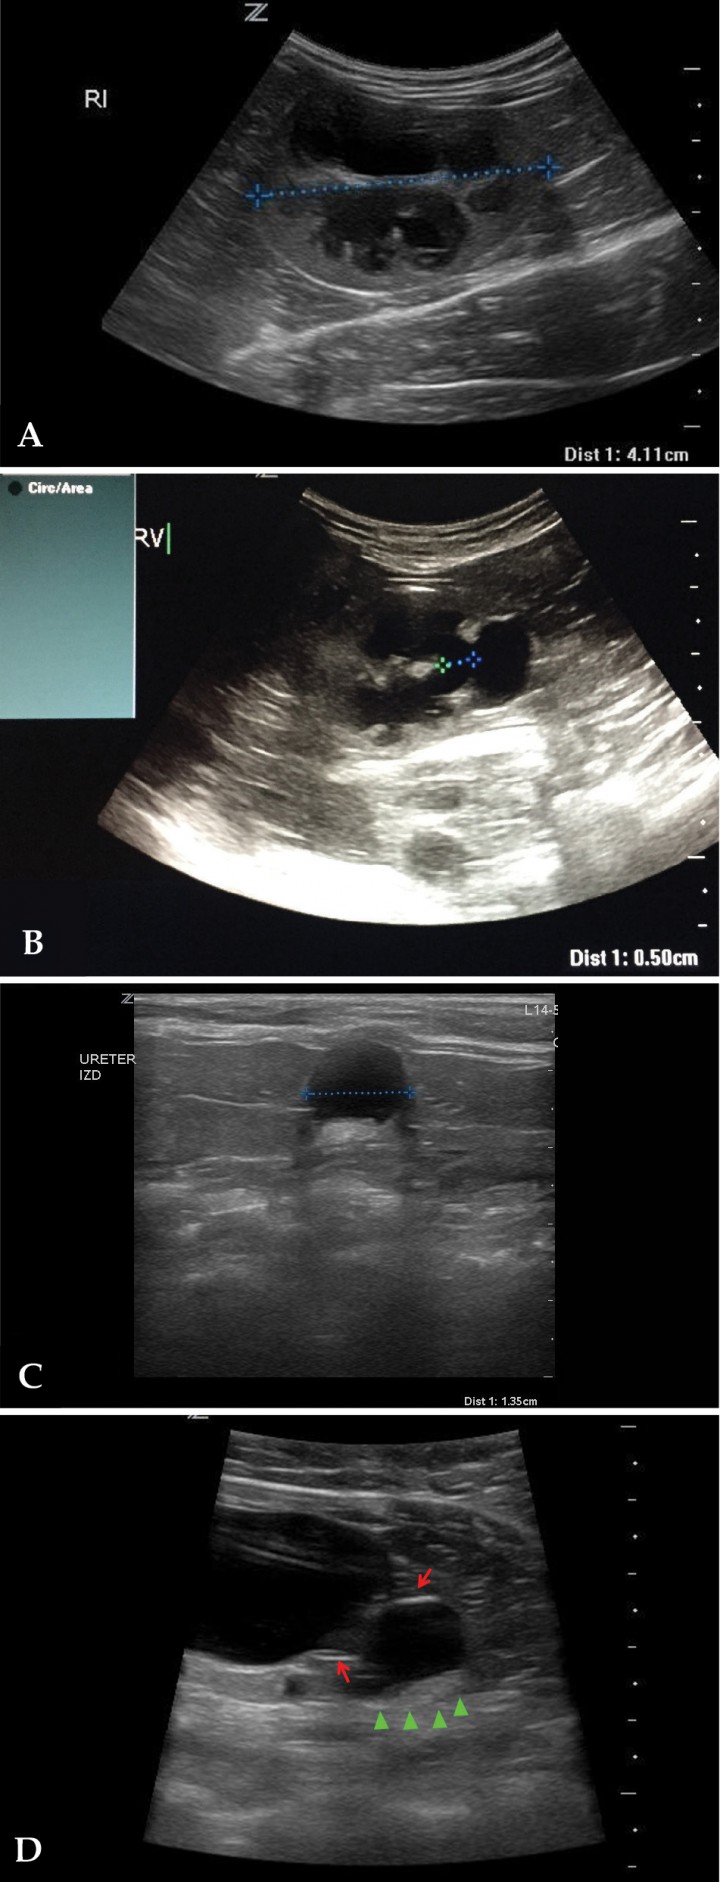

En este caso se realizó una ecografía abdominal, observándose un riñón derecho normal, con una longitud de 3,7 cm; no fue así en el caso del riñón izquierdo, que presentó una longitud de 4,1 cm (Fig. 3A) y una dilatación patológica de la pelvis renal (0,5 cm) con un adelgazamiento de su cortical renal (Fig. 3B). La vejiga de la orina no presentó alteraciones; sin embargo, en la unión ureterovesical se observó una dilatación del uréter (hidrouréter, 1,35 cm) (Figs. 3C y D) y dos líneas hiperecogénicas alrededor de la zona de inserción (Fig. 3D); en esta zona se observó un contenido anecógeno (orina) y una moderada cantidad de sedimento (Fig. 3D).

Figura 3

Imágenes ecográficas del riñón y el uréter izquierdos. (A) Corte longitudinal del riñón, longitud aumentada (4,1 cm). (B) Corte transversal. Se observa pielectasia (0,5 cm). (C) Corte transversal del uréter. Se aprecia hidrouréter (1,35 cm). (D) Corte longitudinal a nivel de la unión ureterovesical. Se observa una dilatación en la unión y unas líneas hiperecogénicas en la desembocadura del uréter (flechas rojas), contenido anecogénico y cierta cantidad de sedimento (cabezas de flecha verdes).